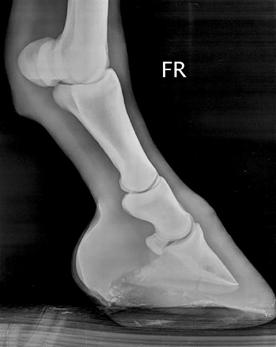

Kulno sąnario OCD (13 pav.) pasireiškia keliose skirtingose sąnario vietose: blauzdikaulio intermedialinėje keteroje, kulno distaliniame lateraliniame skridinyje, rečiau – blauzdikaulio plaktukėliuose ir kulno medialiniame skridinyje (Ross M.W., Dyson S.J., 2003, Bramlage L.R., 2006).

Diagnozuojant ligą, daromos 4 standartinės kulno sąnario rentgenogramos. Tai: dorsoplantarinė, lateromedialinė ir 2 įstrižos projekcijos. Iš jų dorsolateralinė ar dorsoplantarinė mediolateralinė įstrižos projekcijos suteikia daugiausiai informacijos (Ross M.W., Dyson S., 2003, Bramlage L.R., 2006).

13 pav. a) Medialinė įstriža kulnakaulio projekcija. b) Lateralinė kulnakaulio projekcija (cal.vet.upenn.edu ).